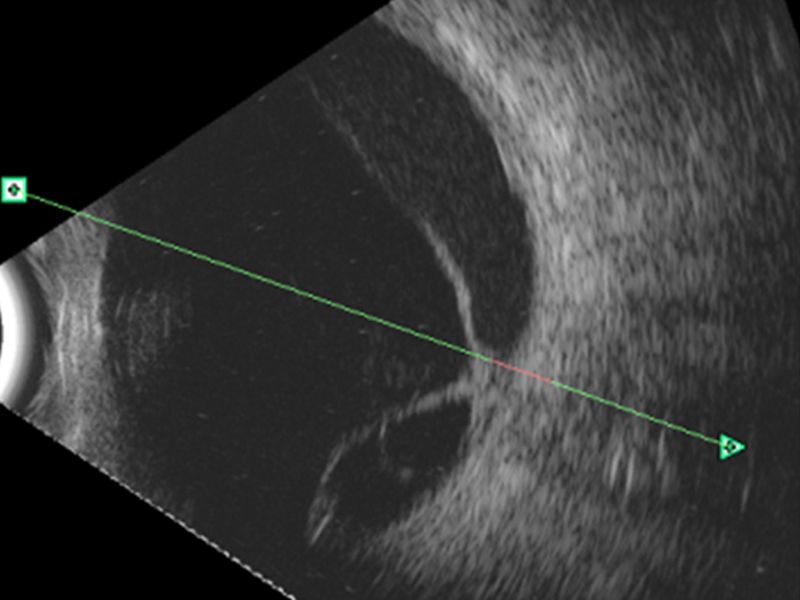

Desprendimiento de retina

Aparece como una membrana continua, de espesor regular y brillante, que puede adquirir diferentes formas (bulloso, plano, en embudo), seguida por un espacio anecogénico (

Figura 10). En modo A, el pico de reflectancia es del 100%, excepto en retinas atróficas o con abundantes pliegues.

Figura 10. Desprendimiento de retina con adherencia al nervio óptico.